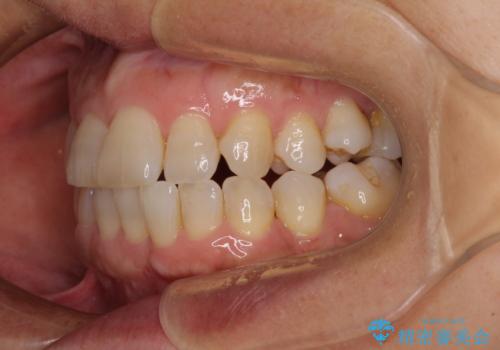

- 骨格的な咬み合わせのズレ、前歯のデコボコとクロスバイトを気にして来院された患者様です。

奥歯の噛みにくさが顕著なためマウスピースではなく、ワイヤー装置による矯正治療を行うこととしました。

下顎の正中を歯1本分ずらした位置とすることで、外見上の骨格的なずれをカバーするように計画しました。

クロスバイトを改善したことで、前歯の負担が軽減し、安定して噛めるようになりました。